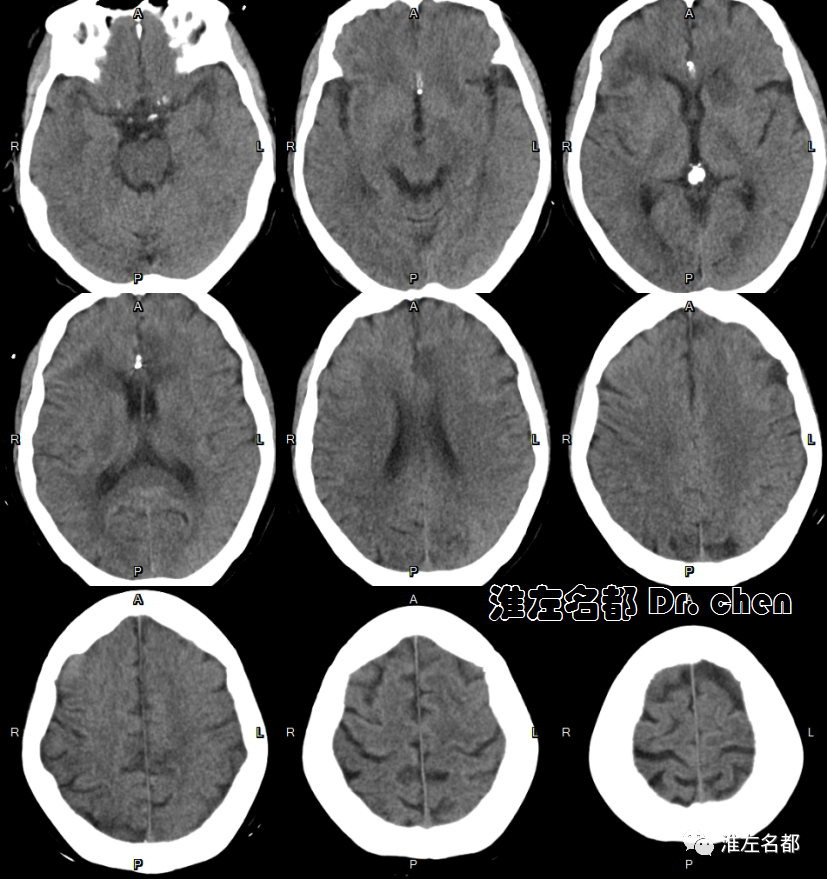

△头颅CT平扫:右侧额叶陈旧性梗死,左侧胼胝体膝部和临近脑组织低密度。

△颅脑CT平扫:左侧大脑前动脉支架(橙箭)植入术后;左侧尾状核头部、胼胝体膝部和临近额叶低密度梗死。

△颅脑CT平扫:左侧尾状核头部、胼胝体膝部和临近额叶陈旧性梗死,局部坏死液化;右侧额叶陈旧性梗死。